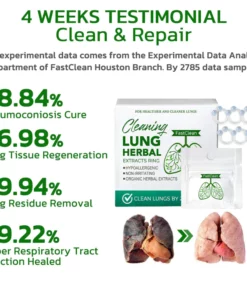

- ✔ Repair damaged airways and lungs

- ✔ Clean the phlegm and garbage accumulated in the lungs

- ✔ Improve and cure respiratory allergies/asthma

- ✔ Prevention of Respiratory Diseases

- ✔ Repair the sequelae of viral pneumonia

- ✔ Allows you to breathe easily again